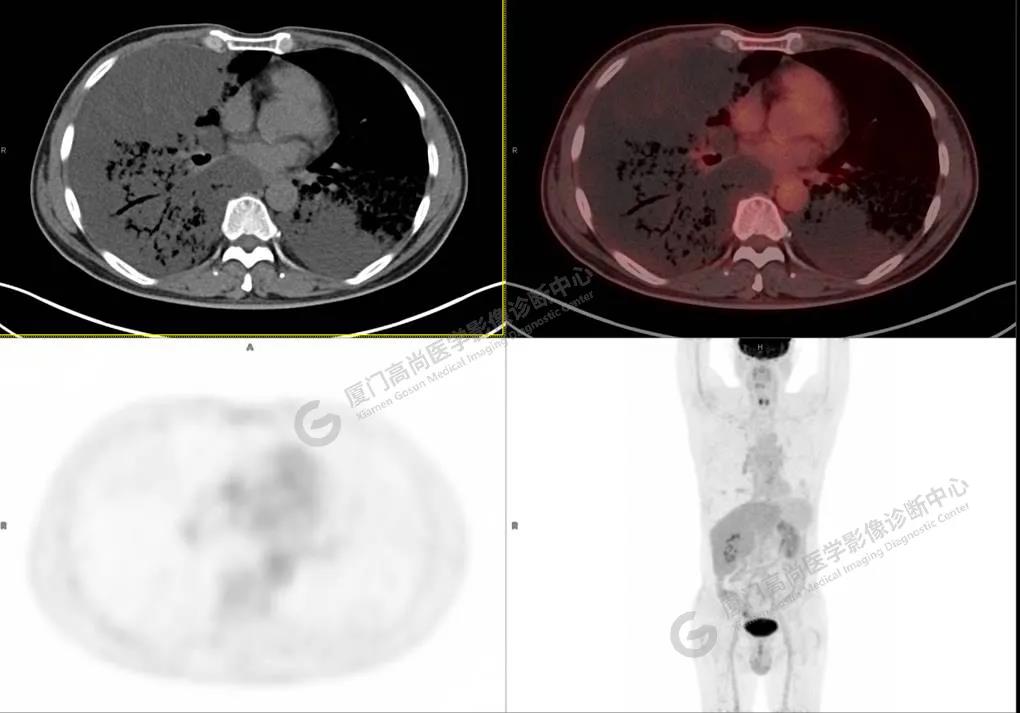

PET/CT影像圖

圖1

圖2

PET/CT所見(jiàn):雙肺大片實(shí)變影及磨玻璃影,部分呈地圖樣改變,累及右肺尖,部分放射性攝取輕微增高,SUVmax 1.77,其內(nèi)見(jiàn)多發(fā)支氣管充氣征象。

影像診斷: 雙肺大片實(shí)變影及磨玻璃影,大部分代謝不高,局部代謝輕微增高,考慮肺泡蛋白沉積癥,建議病理學(xué)檢查或肺泡灌洗物檢查。